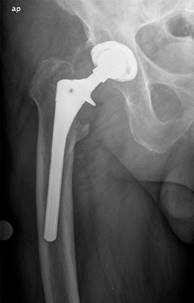

Controles: pacientes con diagnóstico de aflojamiento protésico, sometidos a cirugía de recambio, sin llegar a producirse fractura periprotésica (n = 19) (Figura 1).

Radiológicos: hallazgo en radiografías simples de radiolucencias progresivas de más de 2 mm en dos radiografías espaciadas al menos un año (describiendo su localización según las zonas de Gruen) (Figura 2). También se tuvieron en cuenta otros hallazgos radiológicos como el stress shielding, el fenómeno del pedestal, el desgaste del polietileno o el hundimiento del vástago. Por último, también incluimos pacientes con hallazgos incongruentes en radiografías simples, pero que mostraron signos de aflojamiento en otras pruebas complementarias radiológicas (resonancia magnética, tomografía computarizada y gammagrafía).

Otros parámetros como el stress shielding (Figura 4) o el fenómeno del pedestal tampoco mostraron diferencias estadísticamente significativas. El desgaste del polietileno fue más frecuente en los casos (37.5%) que en los controles (15.8%) y el hundimiento del vástago (Figura 5) fue más frecuente en controles (21.1 vs 0.0%); aunque ninguno de estos resultados fue estadísticamente significativo. El hundimiento del vástago fue menor en los pacientes con vástago con apoyo metafisario (6.3%) que en los casos en los que no se empleó.

Figura 5: Hundimiento del vástago, medido empleando como referencia distancia entre el hombro de la prótesis y la punta del trocánter mayor.